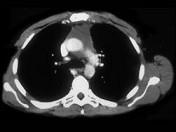

问题 男,64岁,胸部隐痛伴眼睑下垂2月余,请结合影像学检查,选出最可能的诊断 ( )

选项 A.淋巴瘤 B.胸腺瘤 C.胸内甲状腺肿 D.纵隔畸胎瘤 E.间皮囊肿

答案 B